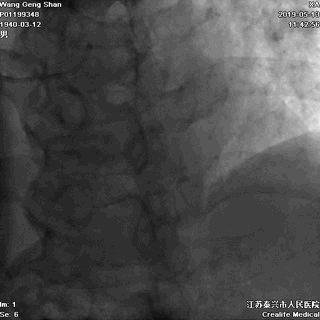

05 LM-LAD支架植入

右头位定位

蜘蛛位定位

LCX球囊拘禁,主支支架释放

回撤LCX球囊

支架球囊再次扩张支架